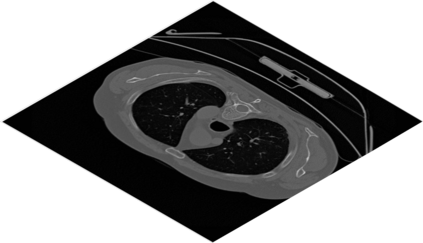

Deep Convolutional Neural Networks (DCNNs) are used extensively in biomedical image segmentation. However, current DCNNs usually use down sampling layers for increasing the receptive field and gaining abstract semantic information. These down sampling layers decrease the spatial dimension of feature maps, which can be detrimental to semantic image segmentation. Atrous convolution is an alternative for the down sampling layer. It increases the receptive field whilst maintains the spatial dimension of feature maps. In this paper, a method for effective atrous rate setting is proposed to achieve the largest and fully-covered receptive field with a minimum number of atrous convolutional layers. Furthermore, different atrous blocks, shortcut connections and normalization methods are explored to select the optimal network structure setting. These lead to a new and full-scale DCNN - Atrous Convolutional Neural Network (ACNN), which incorporates cascaded atrous II-blocks, residual learning and Fine Group Normalization (FGN). Application results of the proposed ACNN to Magnetic Resonance Imaging (MRI) and Computed Tomography (CT) image segmentation demonstrate that the proposed ACNN can achieve comparable segmentation Dice Similarity Coefficients (DSCs) to U-Net, optimized U-Net and hybrid network, but with significantly reduced trainable parameters due to the use of full-scale feature maps and therefore computationally is much more efficient for both the training and inference.